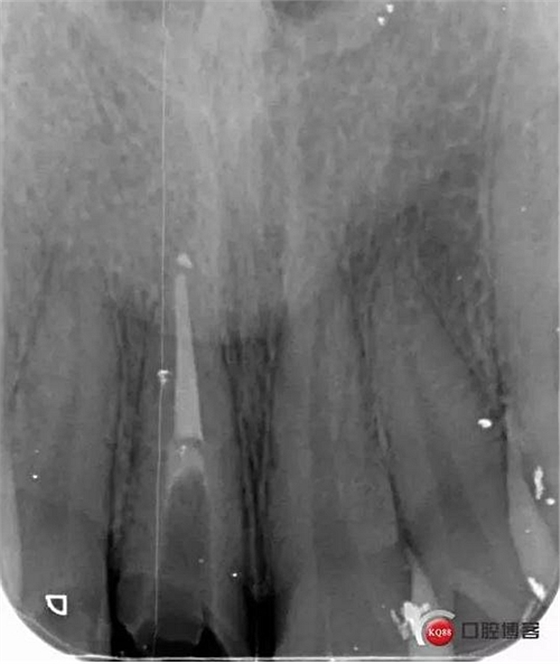

看起來有點(diǎn)頭痛哈,拍片檢查

牙根長度比較號(hào),根充完善。這張片子也可以看出,為什么上次脫落了,樁的深度不夠,而且明顯樁根樁道不匹配,打的樁都沒有到位。